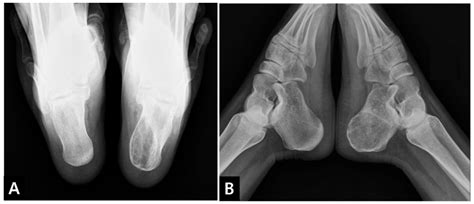

A Calcaneus X Ray is a medical imaging technique used to visualize the calcaneus, or heel bone. This type of X-ray is particularly useful for diagnosing fractures, dislocations, and other abnormalities in the heel area. The calcaneus is the largest bone in the foot and is subject to significant stress and impact, making it prone to injuries, especially in athletes and individuals involved in high-impact activities.

Interpreting the results of a Calcaneus X Ray requires the expertise of a radiologist or orthopedic specialist. The images are carefully examined for signs of fractures, dislocations, or other abnormalities. Here are some common findings that may be identified:

• Fractures: These can range from simple cracks to complex fractures involving multiple bone fragments. The location and severity of the fracture will determine the appropriate treatment.

• Dislocations: These occur when the bones in the heel area are displaced from their normal position. Dislocations can cause significant pain and may require surgical intervention.

• Bone Spurs: These are bony projections that can form on the heel bone due to chronic stress or inflammation. Bone spurs can cause pain and discomfort, especially during weight-bearing activities.

• Arthritis: X-rays can also reveal signs of arthritis, such as joint space narrowing and bone spurs, which can affect the heel and surrounding joints.

A Calcaneus X Ray is a valuable tool for diagnosing a variety of heel injuries. Some of the most common conditions include:

• Calcaneal Fractures: These are fractures of the heel bone and can occur due to falls, high-impact activities, or trauma. They are often classified as intra-articular (involving the joint) or extra-articular (not involving the joint).